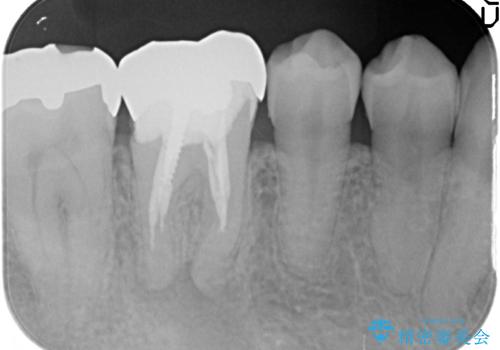

検査の結果X線上で右下6に根尖病変を認めたため、再根管治療を行いました。

症状が治まったのを確認後、オールセラミッククラウンによる補綴を行いました。